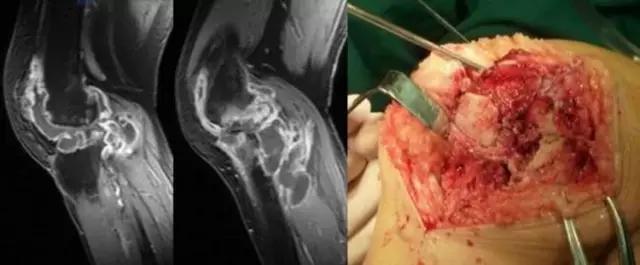

膝关节结核为侵袭性病变,会破坏膝关节的滑膜、软骨、骨等,所形成的寒性脓疡会顺着策划间隙流注,与其他疾病的表现不同。 病例:李XX,女,56岁,右膝关节疼痛逐渐加重8个月。手术及病理证实为膝关节结核。